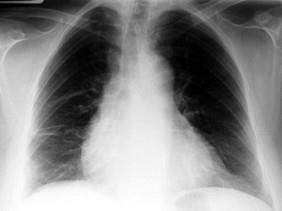

男,59岁,呼吸困难,胸痛,有发热,请结合CT图像选择最可能的诊断 ( )A、肺囊虫病B、肺癌C、肺脓肿D、大叶性肺炎E、脓胸

问题 男,59岁,呼吸困难,胸痛,有发热,请结合CT图像选择最可能的诊断 ( )

选项 A、肺囊虫病 B、肺癌 C、肺脓肿 D、大叶性肺炎 E、脓胸

答案 E